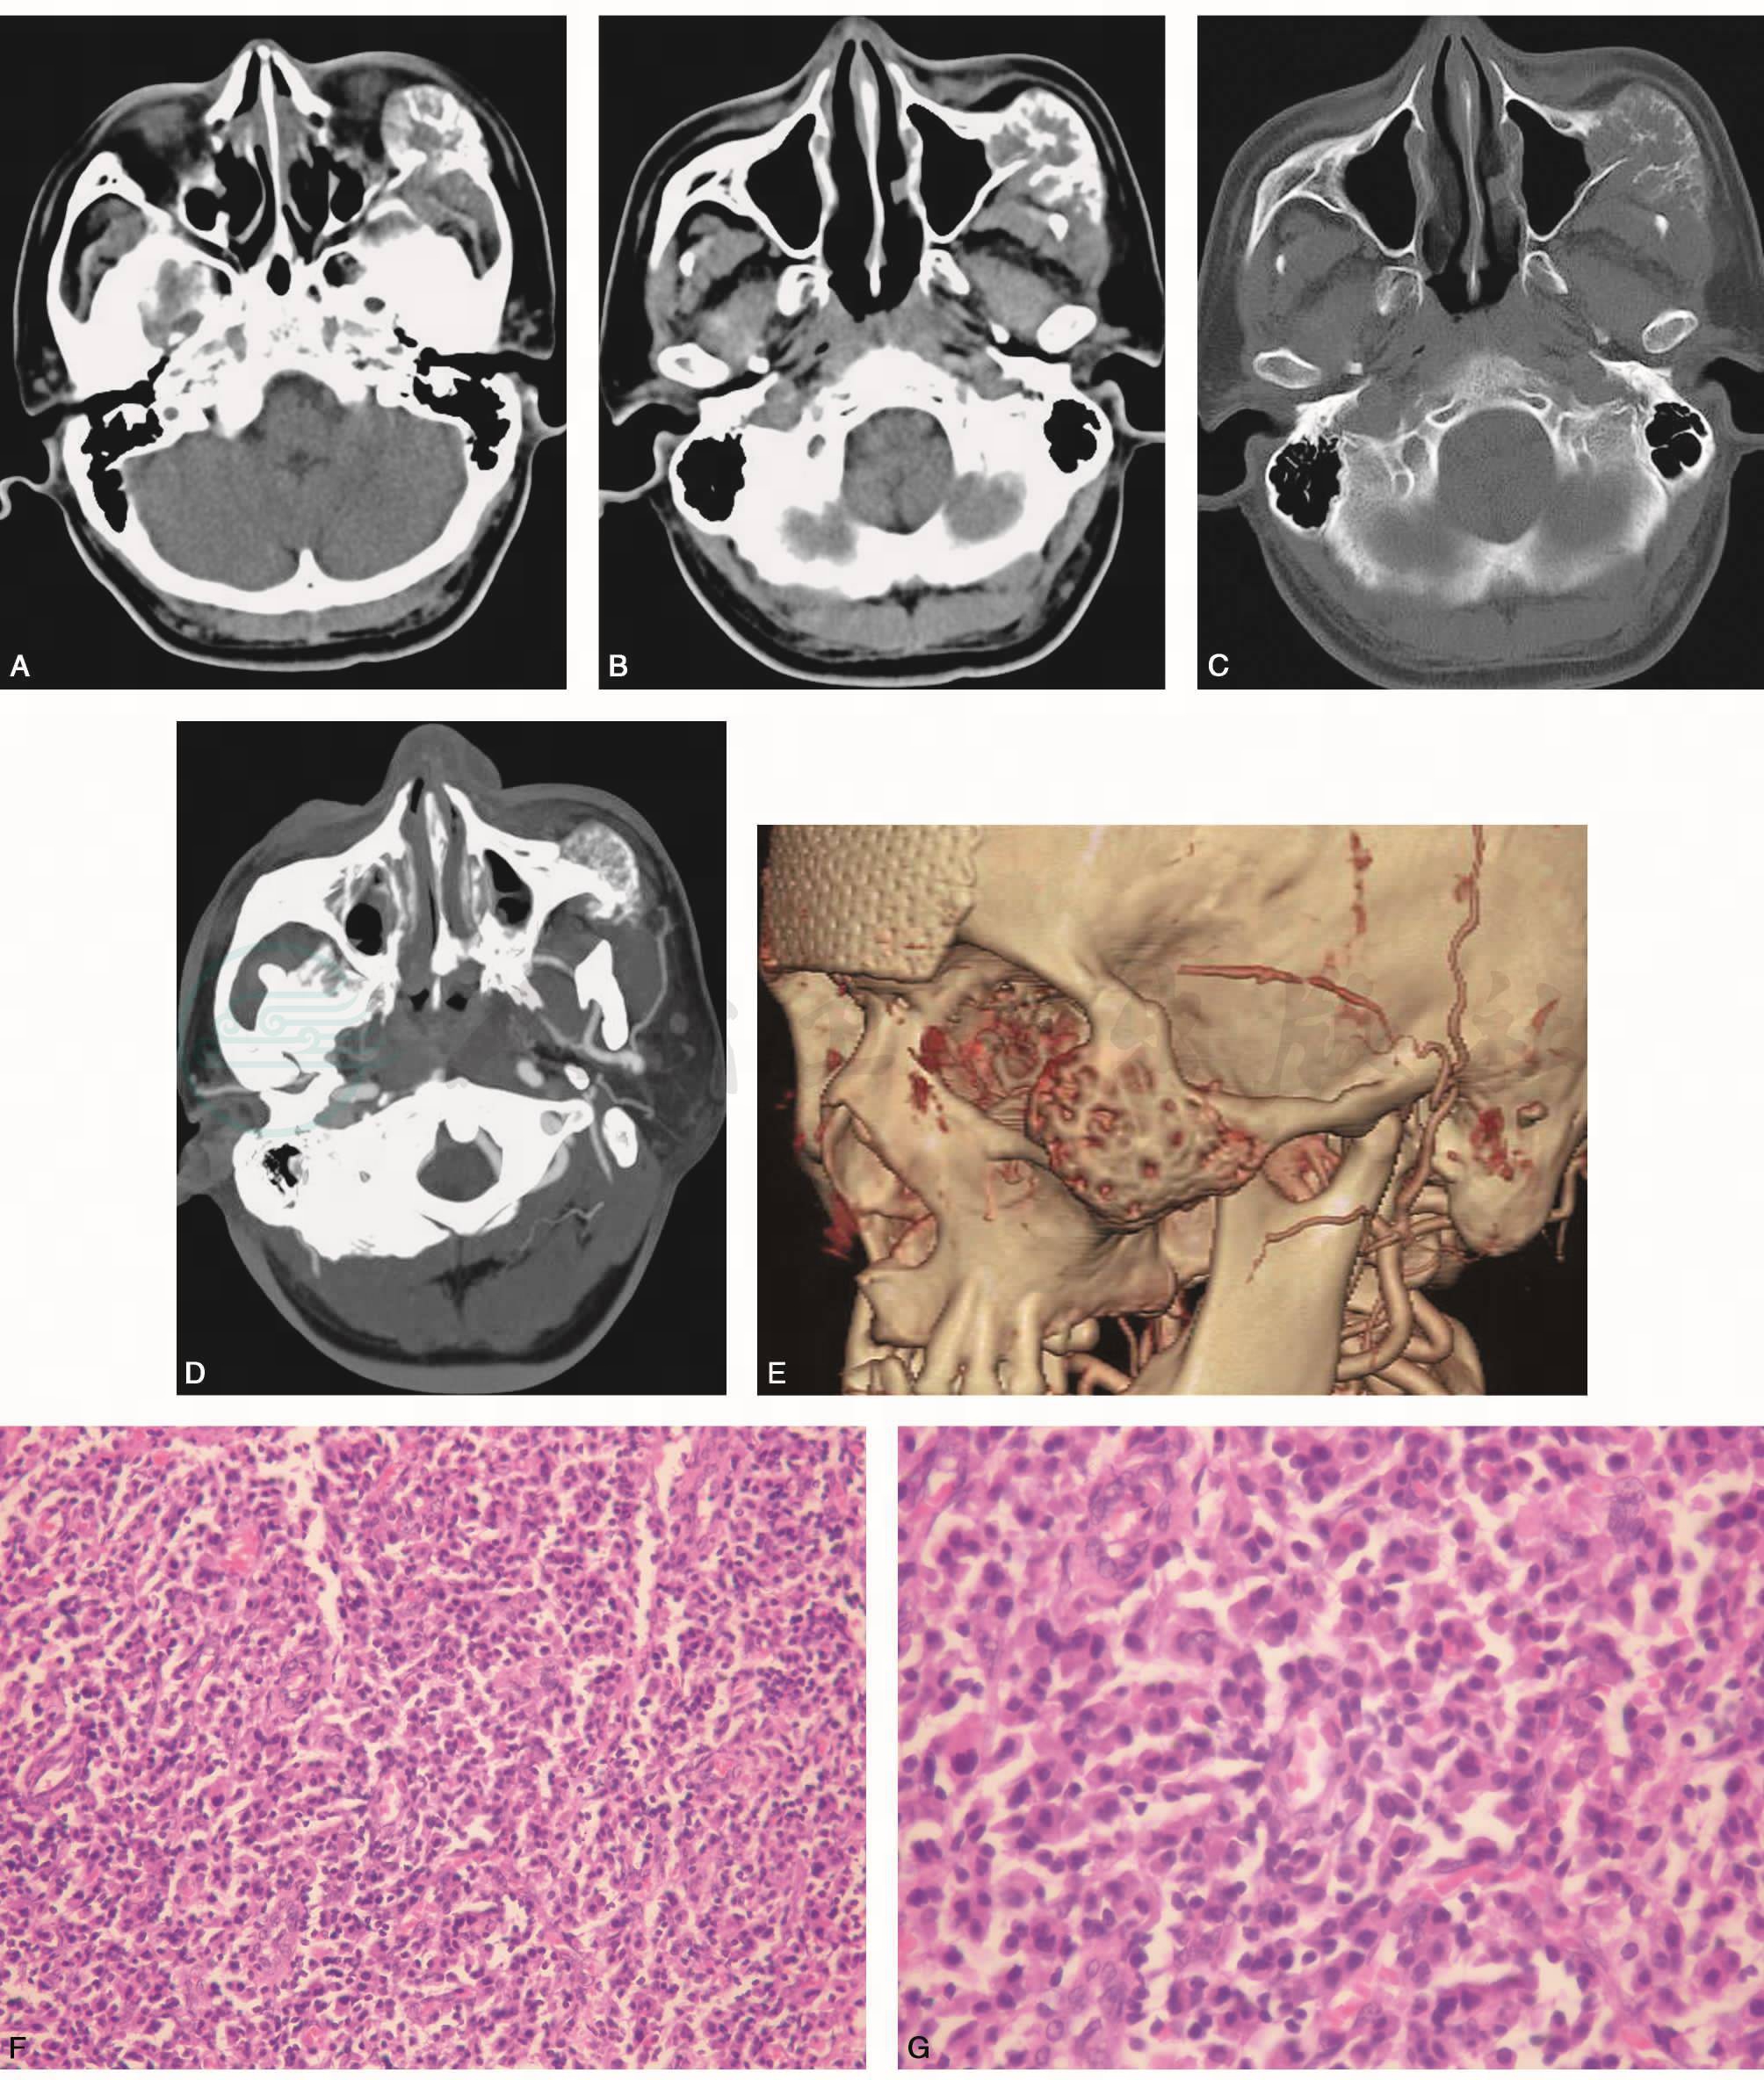

面部CT及三维重建所见:左颧骨、眼眶外侧壁及上颌窦外侧壁交界处可见一约3.5cm×3.0cm的骨质膨胀吸收破坏区,边界清晰,内可见条状骨嵴,增强扫描呈点条状中度强化,边界未见明确强化。三维重建未见明确肿瘤供血动脉,引流静脉为上颌静脉、面静脉(图1)。

图1 上颌骨浆细胞瘤

A~B. CT横断位平扫;C. CT横断位骨窗;D. CT横断位增强片;E.三维重建VR;F. HE×200;G. HE×400

左颧部浆细胞瘤。免疫组织化学:CD38(+),CD138(+),MuM1(+),Lambda(+),Kappa(-),CD56(-),LCA(-),CD20(-),Oct-2(-),Bobl(-),PAX-5(-),CD30(-),CD3(-),VCHL1(-),S-100(-),CD1a(-),HMB45(-),CD34(-),CD68(-),CD117(-),Vim(+),CK(-),CK8&18(-)。